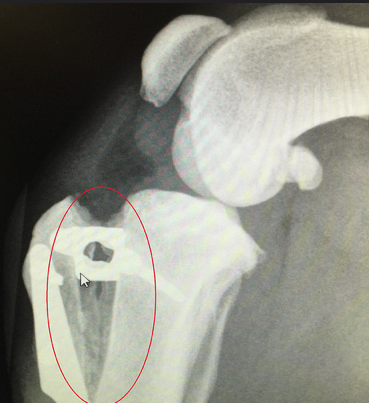

Tibial Plateau Levelling Osteotomy (TPLO)

Another option for CrCl disease treatment is TPLO. It is a more modern procedure, which involves more invasive surgery. A veterinary surgeon will make a circular cut in the tibia and realign the bone, to give a more stable base for the dog to walk on. This movement will be held in place by plates and screws. This method is sometimes preferred for larger, heavier dogs or for more active personalities.

Tibial Tuberosity Advancement (TTA) is similar in approach to TPLO. However, the bone is cut in a linear fashion, in order for the tibia to be moved to a different angle. Like TPLO it requires plates and screws to stay in place initially, and although they are not required after healing they are rarely removed. It also has a long period of recovery, where you will need to keep your dog on limited exercise to reduce the risk of re-fracturing the bone before it has healed.

The surgical procedures of both TTA and TPLO involve cutting the bone to change the angle of the tibial tuberosity in the stifle, using an implant to hold the bones in a different angle while they heal.

The Simitri Stable in Stride® implant is comprised of two, surgical grade stainless steel plates; the femoral (thigh bone) plate and the tibial plate. The femoral plate has a ball and stem that interconnects with the tibial plate via an 8 mm travel channel within the articulating insert.

The insert is composed of ultrahigh molecular weight polyethylene (UHMWPE), this is the same material used in human total hip and knee replacements. The plates are positioned on the inside of the affected leg and attached above and below the knee joint with six cortical locking screws. The entire implant remains outside the knee joint, but under the skin and muscle.